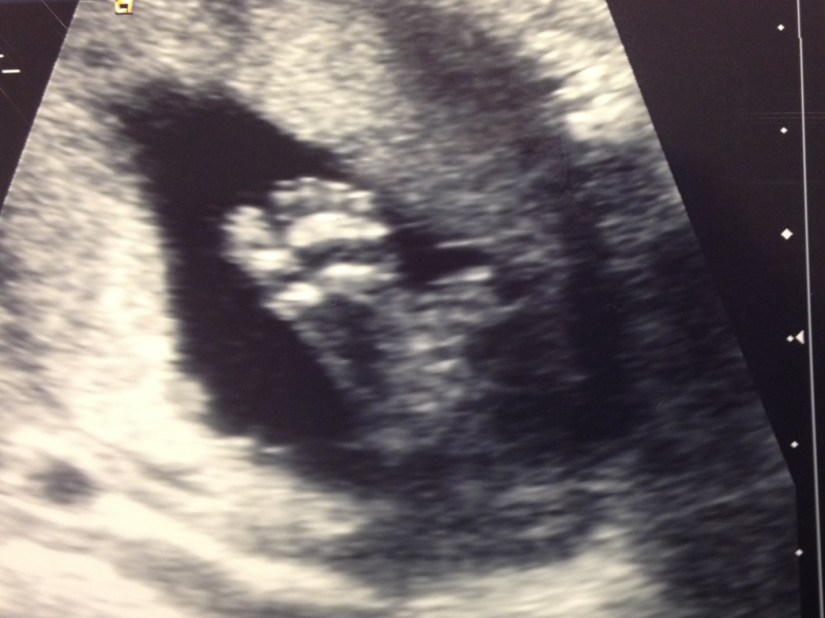

And here are his big feet!

19wkus_feet